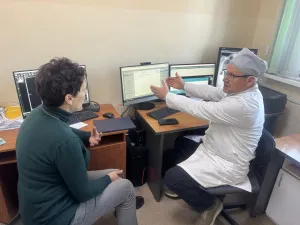

К коллегам – с новыми рекомендациями!

Главный врач ПДККФЦ, главный детский фтизиатр Приморского края Светлана Осина вместе с коллегами посетила Пограничный район по вопросам профилактики туберкулеза – профилактических осмотров и их эффективности.